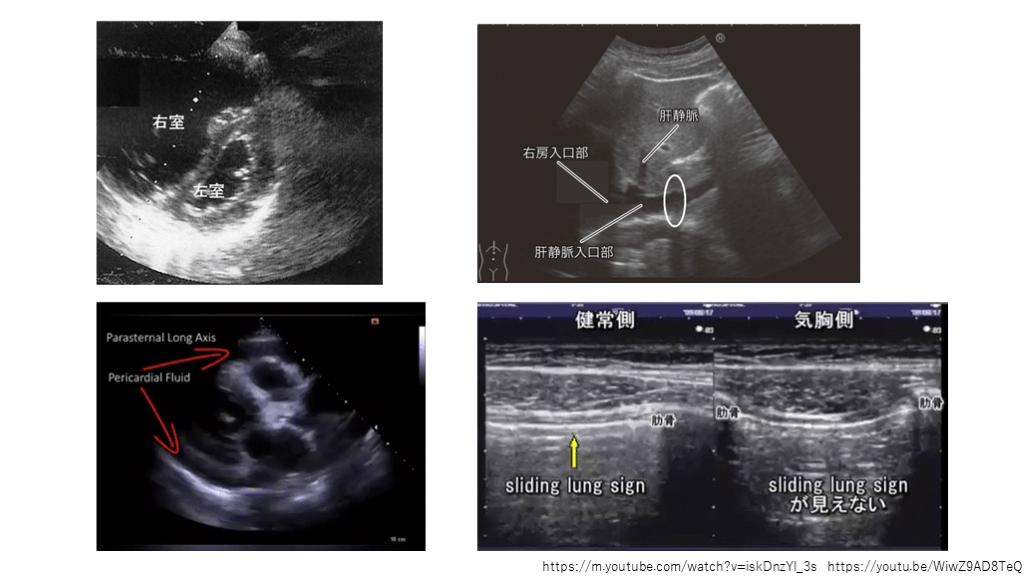

ROSC後   原因検索と鑑別疾患 心肺停止の原因として考えられる疾患は5H5Tで覚える